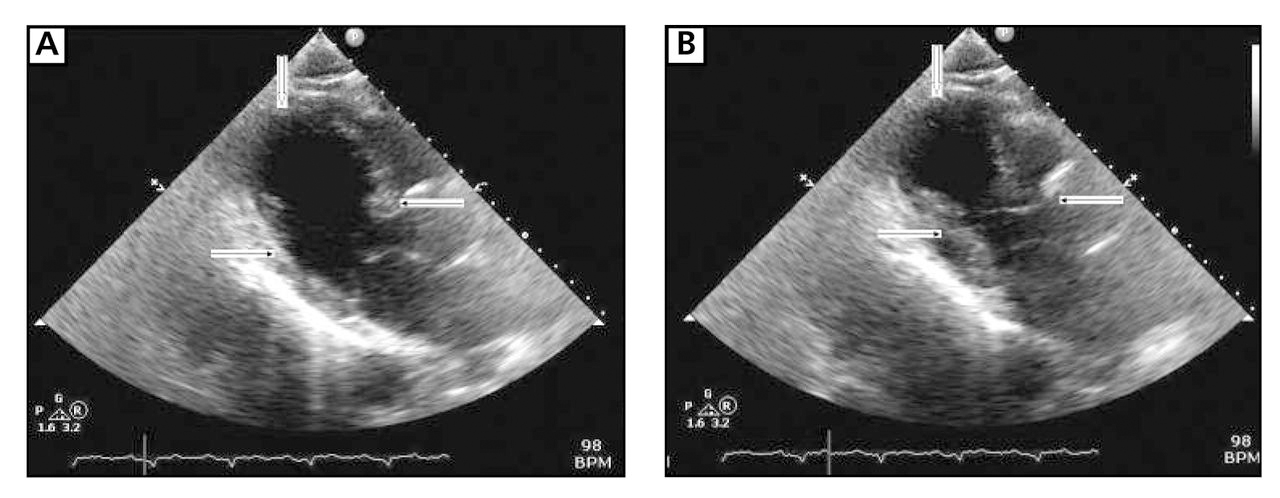

On the night of hospital day 1, the patient complained of midsternal chest pressure radiating to his neck. A second ECG demonstrated diffuse ST-segment elevation in the anterolateral and inferior leads, along with ST-segment depression in lead aVR and absence of ST-segment changes in lead V1 (Figure 1). Cardiac biomarkers revealed a creatinine kinase-MB fraction of 0.192 ng/mL and a troponin I level of 3.23 ng/mL. Immediate cardiac catheterization was performed (early morning of day 2), which revealed no new obstructive lesions in the patient's coronary artery anatomy (Figure 2). Ventriculography was deferred because of renal insufficiency and the recently performed computed tomographic pulmonary angiography. After cardiac catheterization, the patient underwent transthoracic echocardiography, results of which demonstrated a left ventricular ejection fraction of 30% to 40%, basilar hyperactivity, apical dyskinesia, and distal inferior and anterior akinesia (Figure 3).

Long-axis precordial end diastolic (A) and end systolic (B) views from transthoracic echocardiogram immediately after cardiac catheterization demonstrate basilar hyperactivity (line arrows), apical dyskinesia (block arrows), and distal inferior and anterior wall akinesia. The ejection fraction was estimated to be 30% to 40%.